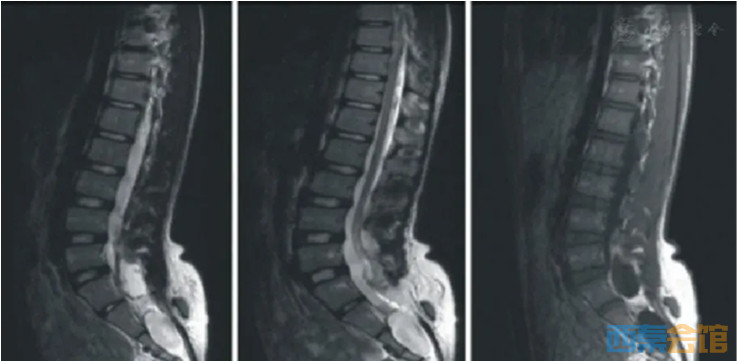

16岁男孩,显示脊柱裂、脊膜膨出、脊髓栓系、骶管囊肿、椎管内硬膜外及皮下脂肪瘤及脊髓空洞改变。